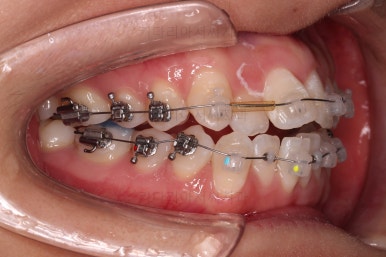

이번 환자분이 선택하신 장치는 데이몬 클리어라고 하는 자가결찰 세라믹 장치인데요.

데이몬 클리어는 현재 사용되는 세라믹 장치 중에 가장 심미성이 뛰어난 장치입니다.

흔히 세라믹 장치로 많이 아시는 클리피씨, 엠파워 클리어 등을 철사를 잡아주는 캡이 메탈로 되어 있어 유심히 관찰하면 메탈 부분이 있는 반면에 데이몬 클리어는 캡 자체도 세라믹으로 되어있어 심미성이 좋습니다.

다만, 통 바디 형태의 세라믹으로 되어있다 보니 강도 증가를 위해서 부피가 약간 더 커진 단점은 있습니다.

교정 시작 9개월만인데요.

벌써 치열이 가지런해졌네요.

입 안의 모습만 보면 조만간 마무리가 가능할 정도로 많은 부분들이 좋아졌는데요.

교정이라는게 단순한 교합/입 안만 보는 것이 아니라 얼굴모습과의 조화, 얼굴모습의 개선까지도 생각해야 되므로 추가적인 고려사항이 많았습니다.

상하좌우 총 4개의 미니스크류를 이용해서 치열을 뒤로 당겨줍니다.

중간평가를 하면서 환자분과 가능한 수준/원하는 수준을 잘 조율해 가면서 입매를 정해갑니다.